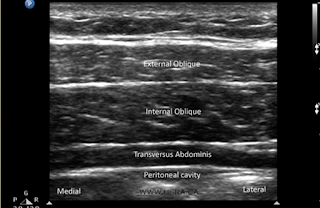

PHONG BẾ MẶT PHẲNG NGANG BỤNG